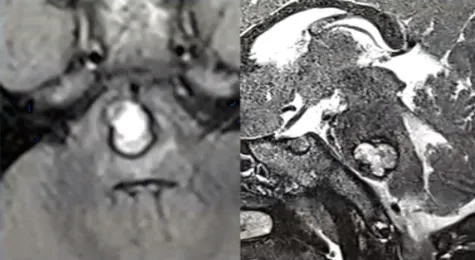

一名活泼好动的3岁男童,突然出现剧烈头痛、左侧肢体瘫痪,右眼也无法外转这是脑干海绵状血管瘤破裂出血的危急信号。作为神经外科极具挑战的手术禁区,脑干出血手术如同在生命中枢上...

3岁的楠楠确诊为脑干海绵状血管瘤,由于孩子年纪太小,又是还未出血的良性病变,一家人慎重选择了保守观察毕竟这种病变一辈子都可能不会出血。 可事实果真如此吗?实际上,儿童脑干海...